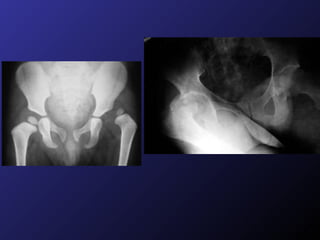

Diagnostico Interrogatorio Exploración Física  Exploración Radiológica

Diagnostico Interrogatorio ExploraciónFísica Exploración Radiológica

Lesiones Asociadas Cápsulafibrosa. Lux. Intracapsular Cápsula y periostio son distendidos por traumatismo, no se atraviesan por hueso lesionado. Lux. Extracapsular Cápsula y periostio son distendidos y atravesados por algún extremo óseo. En ojal Extremo óseo grande queda atrapado en cápsula y extremo pequeño atraviesa cápsula. EG  Cadera.